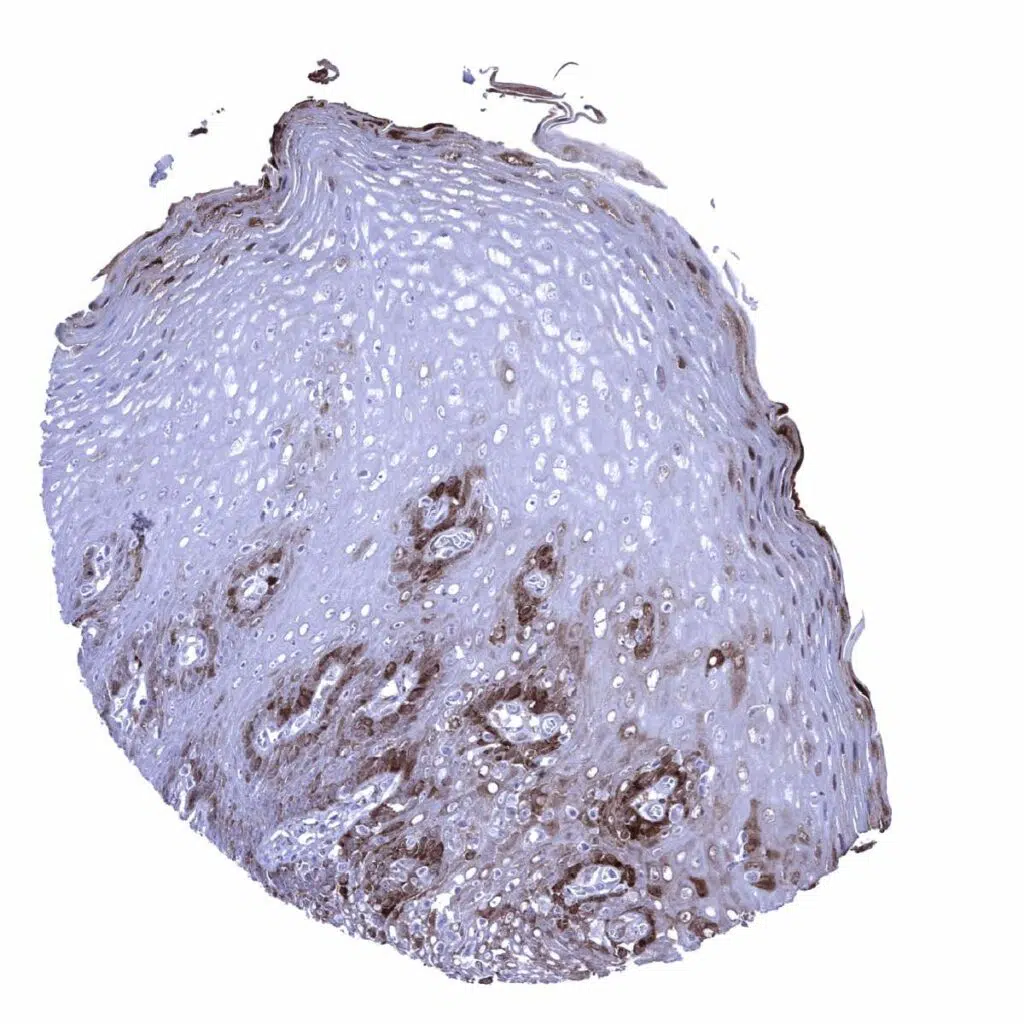

Esophagus, squamous epithelium – A moderate to strong nuclear and cytoplasmic GS staining occurs in the basal and suprabasal cell layers as well as in the top cell layers of the squamous epithelium.